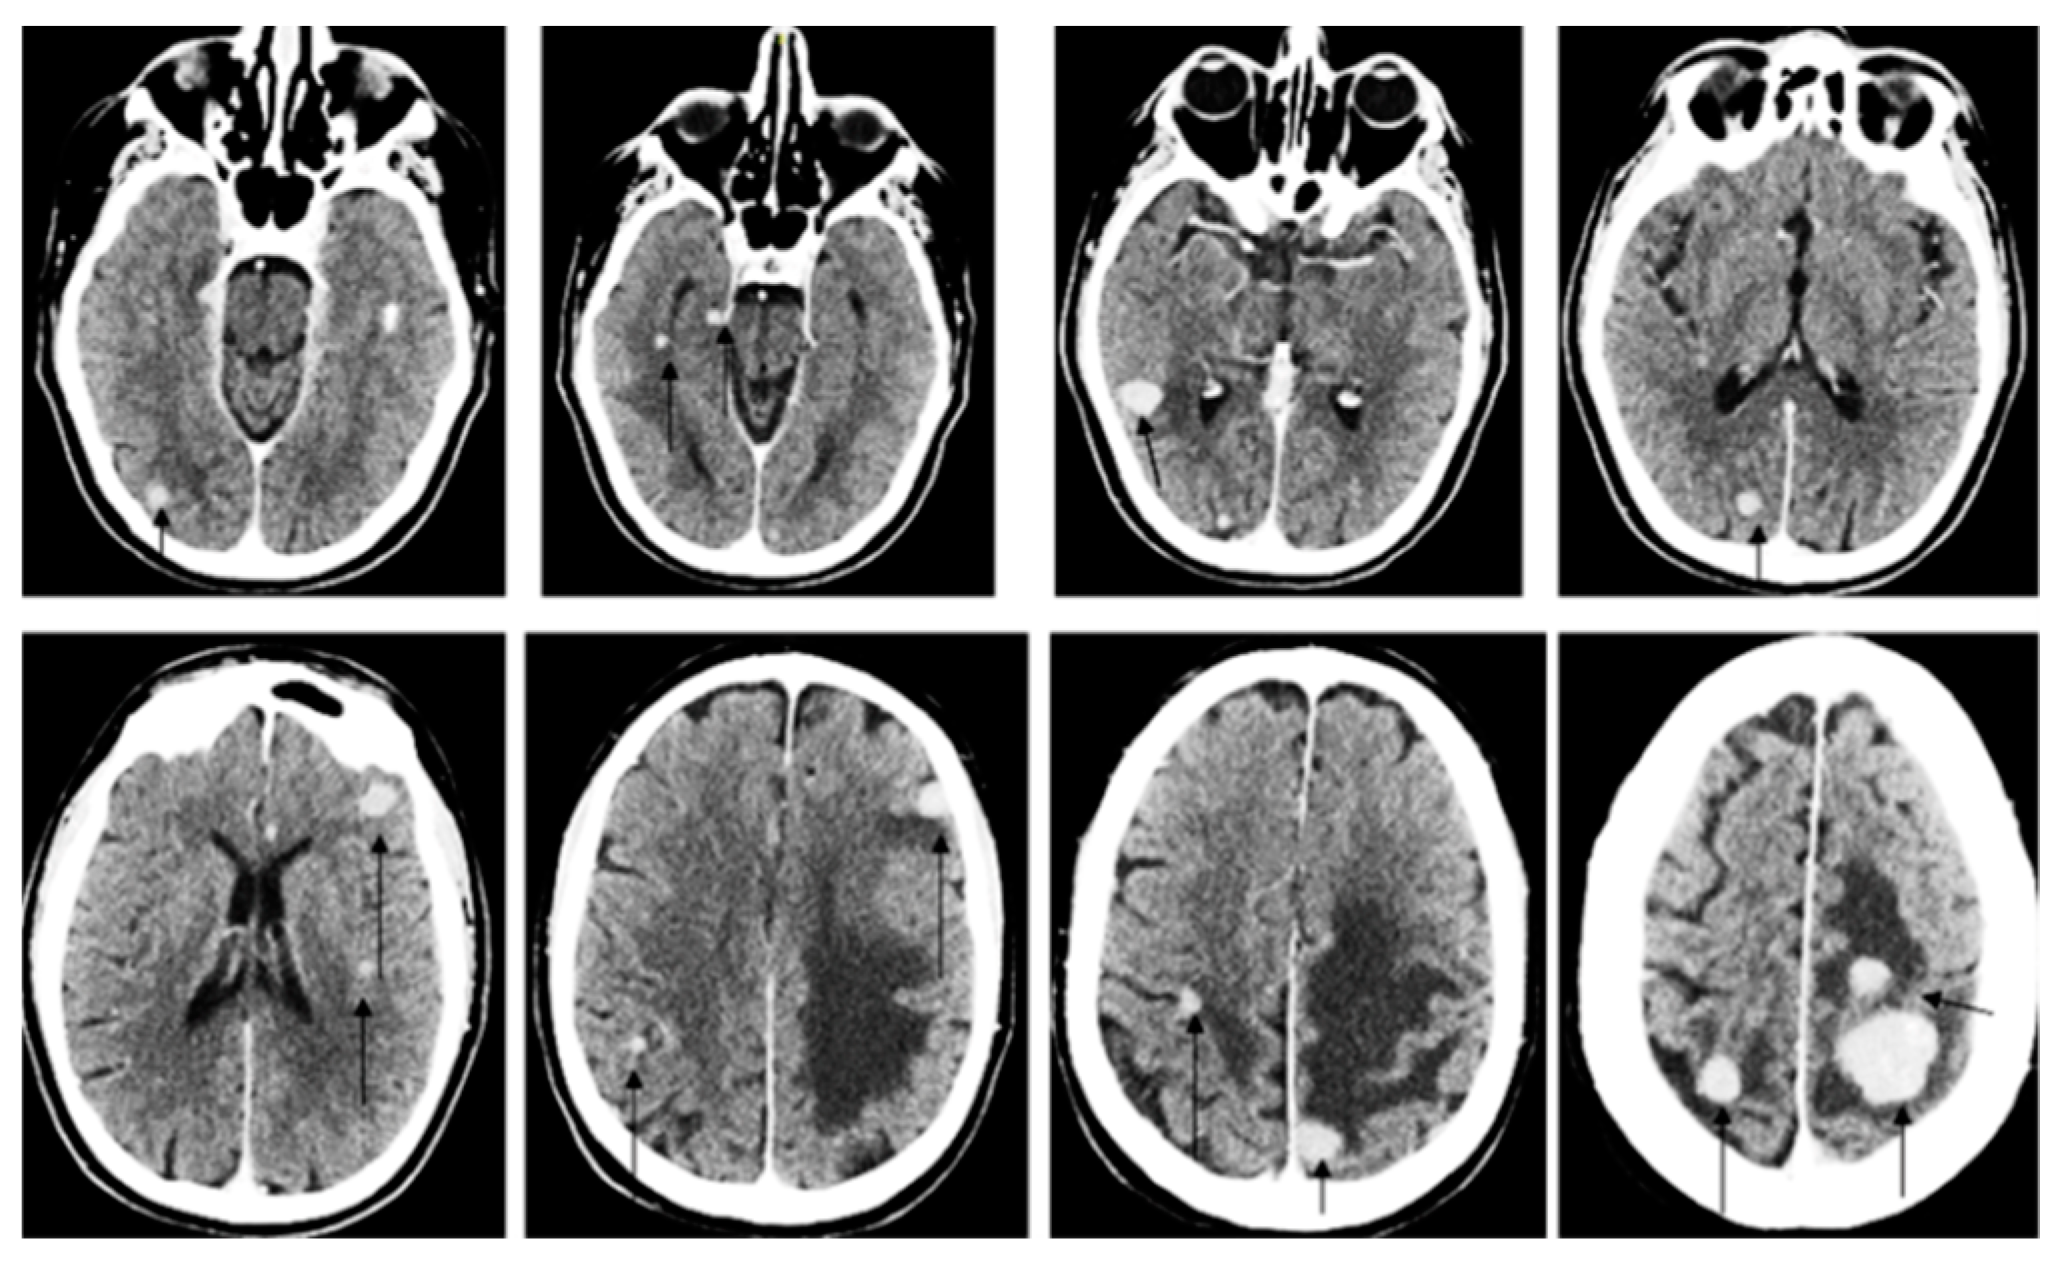

2. Case Report

4. Results